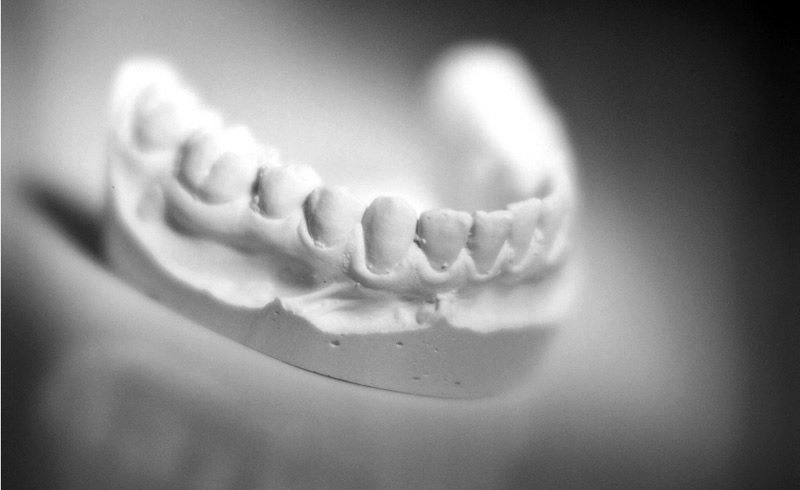

Es gibt unterschiedliche Ursachen, die zu Zahnverfärbungen führen können. Die natürliche, altersbedingte Farbveränderung der Zähne wird durch den Genuss von zahnverfärbenden Substanzen wie z.B. Kaffee, Tee, Cola, Tabak und Rotwein usw. oder Medikamenteneinnahme zusätzlich verstärkt. Durch eine professionelle medizinische Zahnaufhellung in der Praxis können wir diesem Prozess entgegenwirken und ihre Zähne nach einer gründlichen Voruntersuchung mit Bestimmung Ihrer Zahnfarbe und Analyse der Zahnverfärbungsursachen in einer einzigen Sitzung um bis zu 8 Helligkeitsstufen verbessern. Zusätzlich besteht für Sie die Möglichkeit eine kosmetische Zahnaufhellung zu Hause mit individuell für Sie hergestellten Zahnschienen tagsüber oder nachts durchzuführen. Das Aufhellungsergebnis richtet sich bei allen Verfahren nach der Struktur des Zahnes und der Anzahl der Anwendungen.